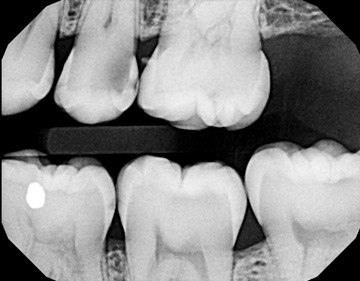

1. Which surfaces shows dental caries?

2. Which surface needs restoration?

4. Which surface needs restoration?

5. Which surface needs restoration?

8. Which surface needs restoration?

9. Which surfaces shows root caries?

10: What is the caries level on occlusal of the tooth # 2.7?

12. Which surface shows Cervical burn out?

13. what are the radiolucency features in mesial and distal root surface of the tooth # 4.5 respectively?

18. Which surfaces need restoration?

32. Which surfaces needs restoration?

38. Which surfaces shows recurrent caries?

40. Which surfaces shows recurrent caries?

41. Which surface shows root caries?

42. Which surfaces shows recurrent caries?

43. Which surface shows recurrent caries?

45. Which surface shows recurrent caries?

46. Which teeth shows recurrent caries?

47. Which surface(s) shows recurrent caries?

48. Which surface does not show caries?

49. Which surface needs restoration?

50. Which surface(s) shows recurrent caries?